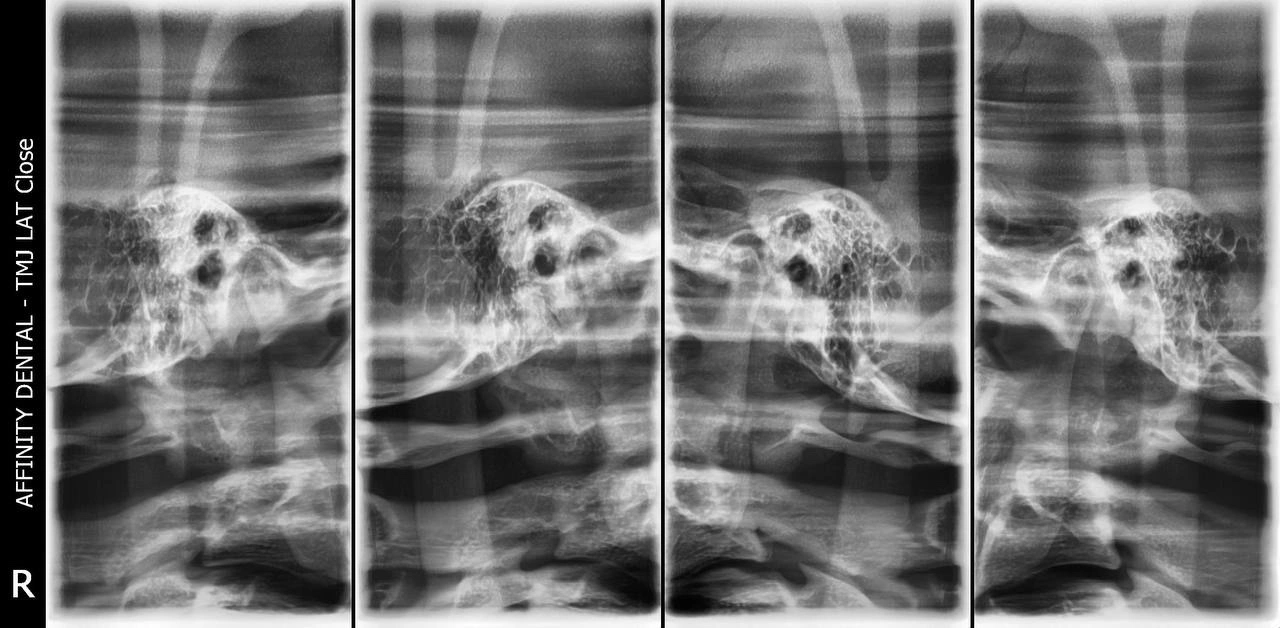

Transcranial X-Ray

Specialized Imaging. A Deeper Look into TMJ and Jaw Health

When patients experience jaw pain, clicking sounds, or difficulty opening and closing their mouths, the issue often lies deeper than the teeth—it may involve the temporomandibular joint (TMJ). At Affinity Dental Clinics, we use a highly specialized diagnostic tool known as the Transcranial X-Ray to evaluate the TMJ and its surrounding structures.

What Is a Transcranial X-Ray?

A Transcranial X-Ray is a type of lateral skull X-ray that focuses on the temporomandibular joint—the hinge that connects your jawbone to your skull, located just in front of your ears. This imaging allows your dentist or oral surgeon to see both the right and left TMJs clearly, in a closed-mouth and open-mouth position.

It captures the position, shape, and alignment of the jaw joints and the surrounding bone structures, helping us evaluate whether something is wrong—and if so, how to address it.

Because this X-ray gives a view of the joint space, bony contours, and condyle position, it is an important tool in determining whether your TMJ is healthy or if there are signs of degeneration, displacement, or inflammation.